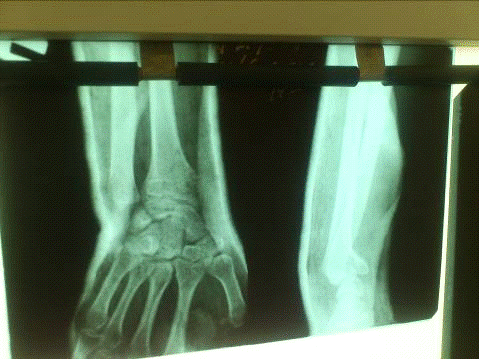

На прицельной рентгенограмме лучезапястного сустава в прямой и боковой проекциях - перелом лучевой кости с тыльным смещением

На рентгенограмме: перелом лучевой кости с тыльным смещением, перелом обеих ветвей правой лобковой кости со смещением отломков

На прицельной рентгенограмме лучезапястного сутава в прямой и боковой проекциях - перелом лучевой кости с тыльным смещением